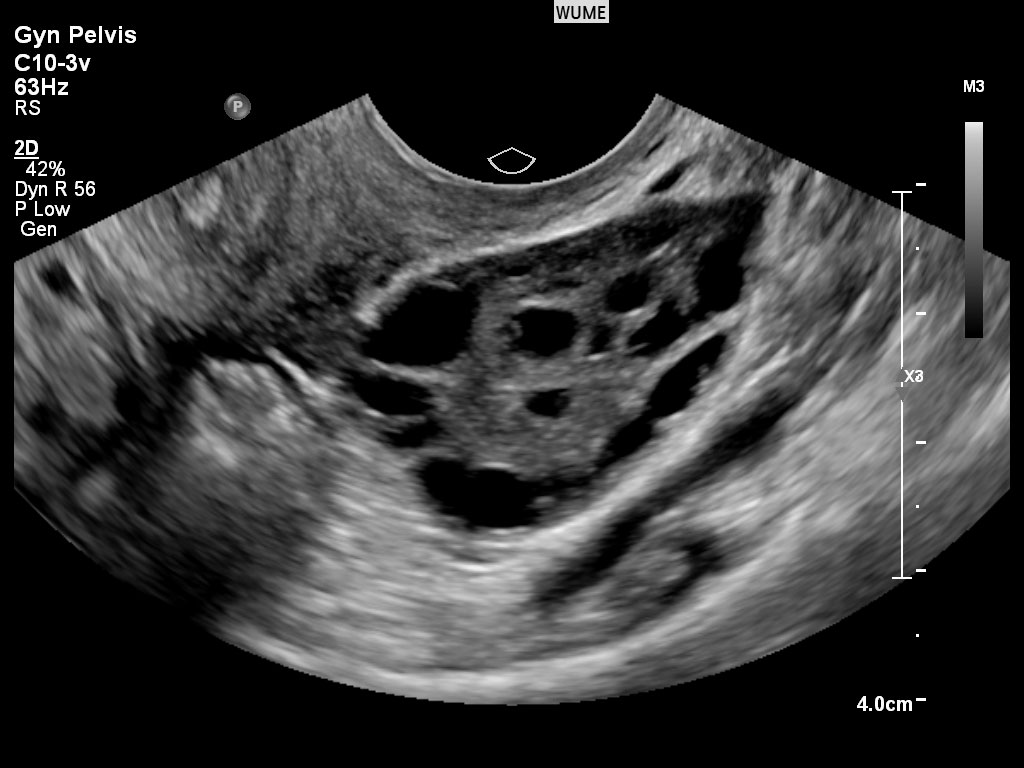

سندرم تخمدان پلی کیستیک (PCOS)

سندرم تخمدان پلی کیستیک (PCOS) وضعیتی است که با پریودهای نامنظم و معمولاً نادر همراه است. برخی از زنان آکنه +/یا افزایش وزن را به عنوان تظاهرات PCOS مشخص کرده اند. بسیاری از ویژگی های اولتراسوند PCO به تشخیص و نظارت بر این بیماری کمک می کند.